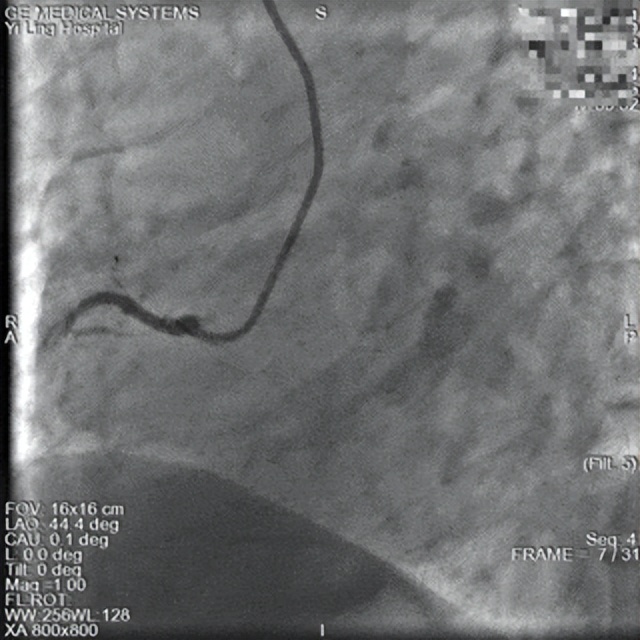

术前

一位66岁男性患者,因外出活动后突发胸痛,症状持续40分钟未缓解,紧急来我院就诊。急诊心电图提示急性下壁心肌梗死,急诊科立即启动导管室应急预案。

心血管病科一病区葛岳鑫副主任接到急诊电话后,带领介入团队迅速响应,于17时35分为患者行急诊冠脉造影,结果显示右冠状动脉中段100%闭塞。团队立即实施急诊PCI术,成功开通右冠并置入支架1枚,手术于17时53分顺利完成,全程仅用时18分钟。